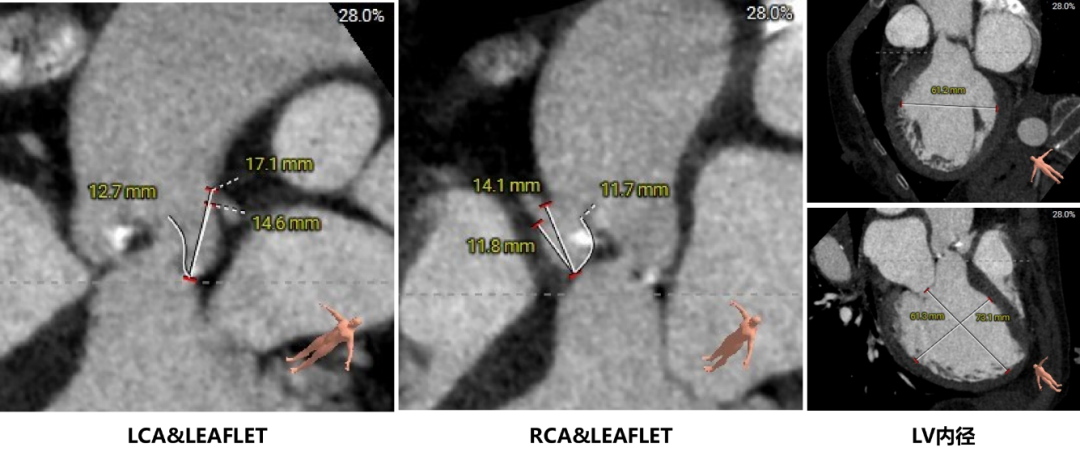

主动脉根部评估:

瓣环上结构测量:

冠脉高度、瓣叶长度及左室内径: